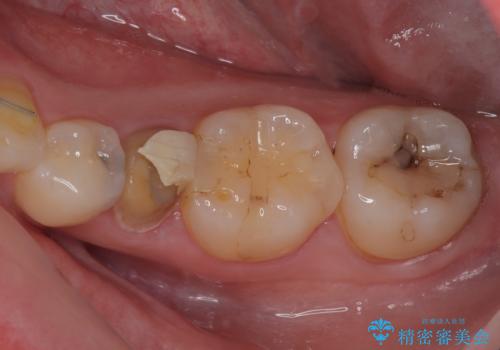

銀歯の下の虫歯を治したい オールセラミッククラウン・セラミックインレー修復